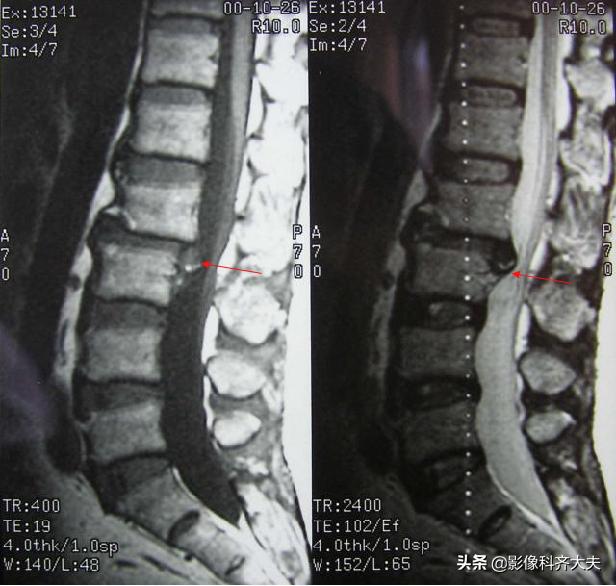

MRI:腰 5-骶1间盘脱出

MRI:腰椎间盘脱出

MRI:髓核游离